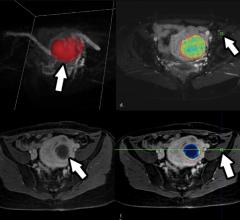

Interventional radiology uses tools like angiography X-ray systems to provide minimally invasive medical diagnosis and treatment using images.

October 26, 2022 — CIVCO Radiotherapy, a global provider of radiotherapy solutions, has announced it is joining forces ...